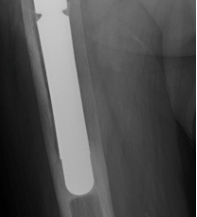

What are the signs of uncemented implant failure?

What are the complications of uncemented prosthesis?